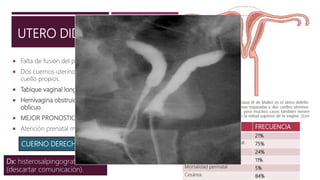

UTERO DIDELFO

 Falta de fusión del par de conductos de Muller.

 Dos cuernos uterinos separados, cada uno con cavidad y

cuello propios.

 Tabique vaginal longitudinal.

 Hemivagina obstruida por un tabique transverso u

oblicuo.

 MEJOR PRONOSTICO EN REPRODUCCION.

 Atención prenatal mas oportuna y precisa.

Dx: histerosalpingografia

(descartar comunicación).

CUERNO DERECHO

COMPLICACIONES FRECUENCIA

Aborto espontaneo 21%

Índice de supervivencia fetal. 75%

Prematurez 24%

Restricción del crecimiento. 11%

Mortalidad perinatal 5%

Cesárea. 84%